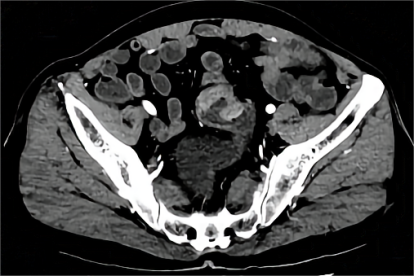

乙状结肠CT图片

乙状结肠为结肠的一部分,呈乙字形弯曲。上承降结肠,下接于直肠的一段结肠。有系膜固定,是憩室、肿瘤的好发部位。

乙状结肠位于左腹下部及小骨盆内,自左侧髂嵴处接降结肠,至第3骶椎上缘处续于直肠,呈“乙”状或“S”形弯曲。正常人除腹壁过厚者外,在左下腹可以触及,呈光滑、稍硬的圆桶状,粗细如蜡烛。小儿因年龄的不同而粗细不等,无压痛。